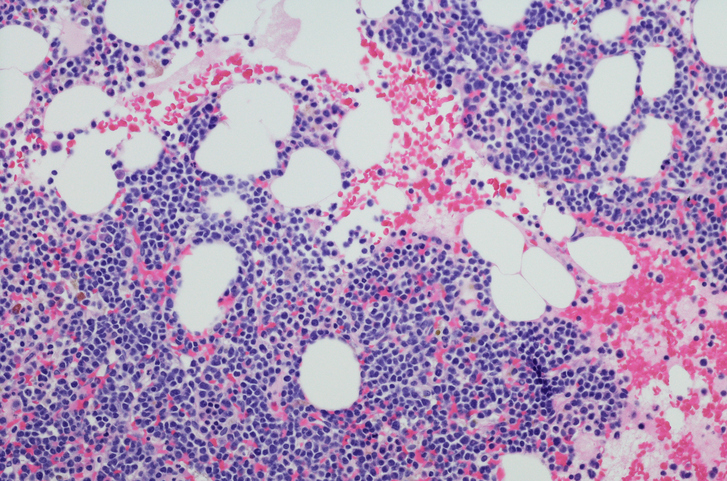

Micrograph of myeloma neoplasm from bone marrow biopsy.

Multiple myeloma is a cancer of the B Lymphocyte cells that produce antibodies. Unlike healthy white blood cells that can produce enough antibody variants to match the numerous harmful pathogens, multiple myeloma causes generation of an abnormal white blood cell population that produces huge amounts of a single type of antibody.